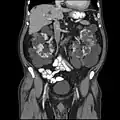

Abdominal CT scan of an adult with autosomal dominant polycystic kidney disease: Extensive cyst formation is seen over both kidneys, with a few cysts in the liver, as well. (Coronal plane)